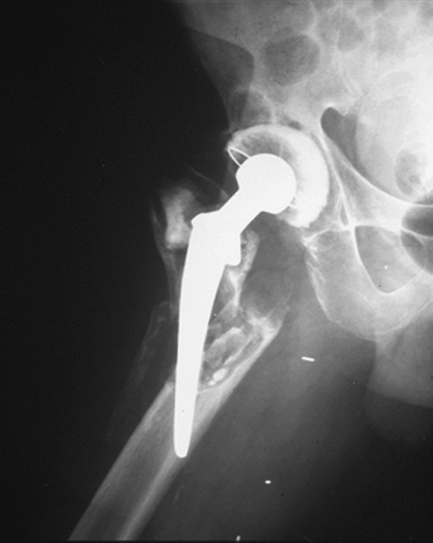

to be one of the most devastating complications for the patient and

surgeon following prosthetic hip replacement. Infection may be seen as

an acute process or may be chronic. Radiographic findings in the acute

setting are often absent and in the chronic setting may be subtle. The

chronically infected prosthetic joint may present with periprosthetic

bone resorption, frank bony destruction, and mechanical failure of the

prosthesis.

![]() |

|

Figure 2-15 Anteroposterior radiograph of the femur demonstrates periprosthetic bone resorption secondary to infection.